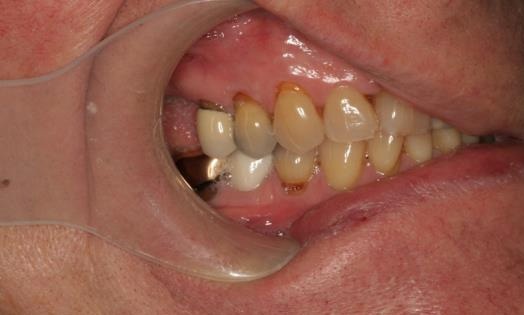

Intraoral clinical exam

- Teeth with exposed root surfaces from gingival recession

- Discoloration of teeth

- Supraerupted teeth

- Abfractions

- Wear facets on posterior teeth and restorations

Final Intraoral Photographs